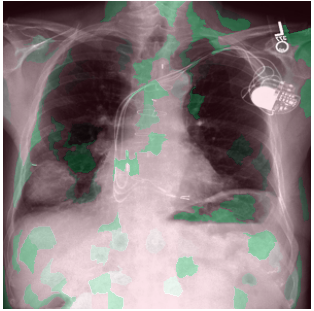

3.3 Interpretability

Post-Hoc Comparisons. We compare our concept-based explanations to post-hoc XAI techniques LIME and SHAP, applied to the baseline InceptionV3 model. The image explanations generated by these techniques disagree with each other and the medical ground truth. We show an example of this observation in Figure 7, where both techniques fail to capture the large mass in the X-ray, and highlight irrelevant regions such as areas outside of the lung as incorrectly important to the classification decision. In contrast, our approach correctly identifies the presence of a mass. More examples are shown in Figure 10.

Refer to caption

(a) Ground Truth

(b) LIME

(c) SHAP

(d) CXR-LLaVA Generated Report

(e) Our Approach

Figure 7: Example of our explanation approach outperforming LIME, SHAP and CXR-LLaVA. Ground truth (a) is a “Large right upper zone mass". LIME (b) and SHAP (c) fail to capture the mass in the X-ray. Most important image regions are bounded by yellow for LIME, and shown in more vibrant green for SHAP. CXR-LLaVA (d) generates a report which wrongly describes the image as non-cancerous. Our approach (e) correctly identifies the presence of a mass.

(a) Ground Truth 1

(b) Ground Truth 2

(c) Ground Truth 3

(d) Ground Truth 4

(e) LIME 1

(f) LIME 2

(g) LIME 3

(h) LIME 4

(i) SHAP 1

(j) SHAP 2

(k) SHAP 3

(l) SHAP 4

Figure 10: Examples of LIME and SHAP explanations failing to capture the medical ground truth of a cancerous chest X-ray, while also generating conflicting explanations. Ground truth (a,b,c,d) is shown as red squares. Most important regions are bounded by yellow for LIME (e,f,g,h) and shown as more vibrant green for SHAP (i,j,k,l).